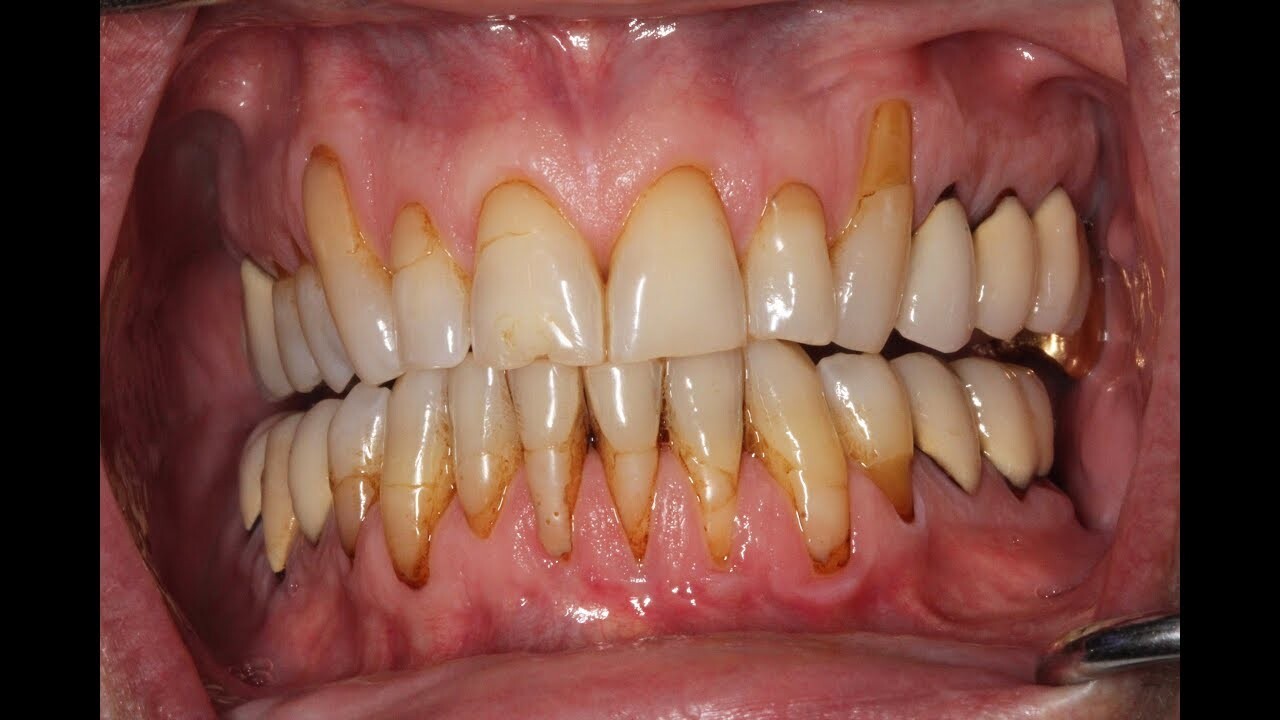

Can vaping cause receding gums?

Yes, vaping can lead to receding gums due to the toxic chemicals found in e-cigarette liquids. Every puff of a vape pen contains 700 toxins, several of which are known carcinogens and can lead to disease when inhaled. While the long-term consequences of vaping have yet to be studied, it is essential to note that people who also vape generally face higher risks than non-smokers for multiple types of cancer, gum infections and receding gums. Educating oneself on the potential risks and benefits associated with vaping will better ensure one’s well-being in the long run.

Yes, dentists can tell if you vape by looking for signs of it in the mouth. These include dryness or inflammation of the gums, discoloration, and a burning sensation when oral tissues are touched or probed. Additionally, the chemicals found in e-cigarette liquids will leave a specific residue on surfaces like teeth and tongue that can be observed during an examination and on the inside of your cheeks and lips. Additionally, if you vape too often, there may also be a noticeable discolouration in the teeth which will give away that you are a regular vaper. However, even if these signs are present it does not necessarily mean that you have gum disease. It is important to continue to practice good oral hygiene and seek regular check-ups with your dentist to ensure that any issues are caught as early as possible.